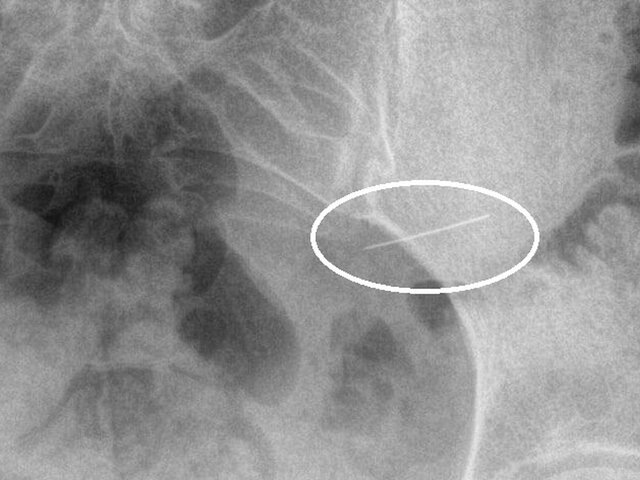

Специалисты Красногорской больницы оказали помощь девушке, поступившей в медучреждение из-за случайно проглоченной швейной иглы. Об этом заявили в пресс-службе Минздрава Подмосковья. По итогам рентгенологического исследования врачи обнаружили, что инородное тело находилось в желудке. Пациентку направили на срочное хирургическое вмешательство. В ходе операции медики успешно извлекли острый предмет при помощи эндоскопического оборудования. Благодаря своевременно выполненной процедуре пациентка избежала серьезных осложнений, таких как перфорация стенок желудка или кишечника, кровотечение, перитонит и сепсис. После вмешательства девушку выписали домой под амбулаторное наблюдение врача-хирурга. Ранее стало известно, что во Владивостоке медики прооперировали женщину с гигантским камнем в почках.

По итогам рентгенологического исследования врачи обнаружили, что инородное тело находилось в желудке. Пациентку направили на срочное хирургическое вмешательство.